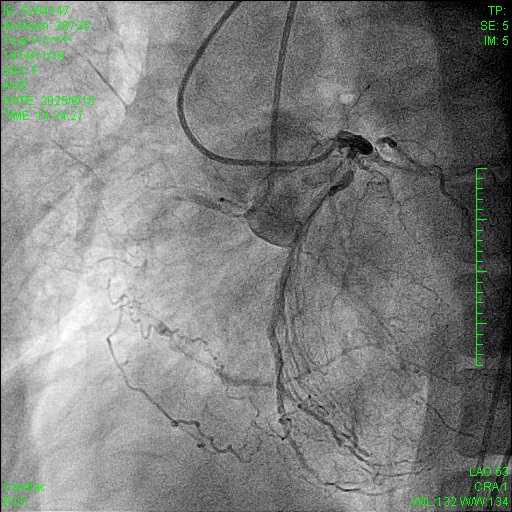

Current angiography showed ISR of the proximal LAD. Regarding the RCA CTO, the J-CTO score was 3 based on lesion calcification, long lesion length, and bending. Collateral circulation was observed through septal collaterals from the LAD and epicardial collaterals from the left circumflex artery, classified as Werner CC2 and J-channel score 0.

The pLAD ISR was treated first with balloon dilatation followed by DES implantation. An antegrade wire escalation strategy up to Conquest Pro 8-20 for RCA CTO was attempted without success. The wire was left in the subintimal space while a retrograde Sion wire supported by a Finecross microcatheter was advanced through a septal channel to reach the distal CTO cap. The retrograde wire was then exchanged for Gaia 2 and XTA for distal CTO cap penetration. However, a kissing wire technique could not be achieved within the CTO body. Following multiple unsuccessful attempts, the Carlino technique was performed via both the antegrade and retrograde microcatheter. Although a retrograde Fielder FC wire could cross the lesion to the antegrade guiding catheter, this could not be followed by a microcatheter. The retrograde Fielder FC wire was then advanced into the antegrade Tornus microcatheter which also couldn¡¯t cross the lession. Consequently, the retrograde wire was exchanged to RG3. Successful tip-in and externalization with RG3 was achieved afterwards. An antegrade 1.0mm balloon failed to traverse the heavily calcified CTO segment. Therefore, antegrade rotational atherectomy was performed using a 1.25mm burr over the RG3 wire. Following that, the Tornus microcatheter was able to cross the lesion into the distal RCA. A Sion wire was advanced to the distal RCA and the RG3 wire was retrieved. Subsequent balloon dilatation and implantation of two DES were successfully completed